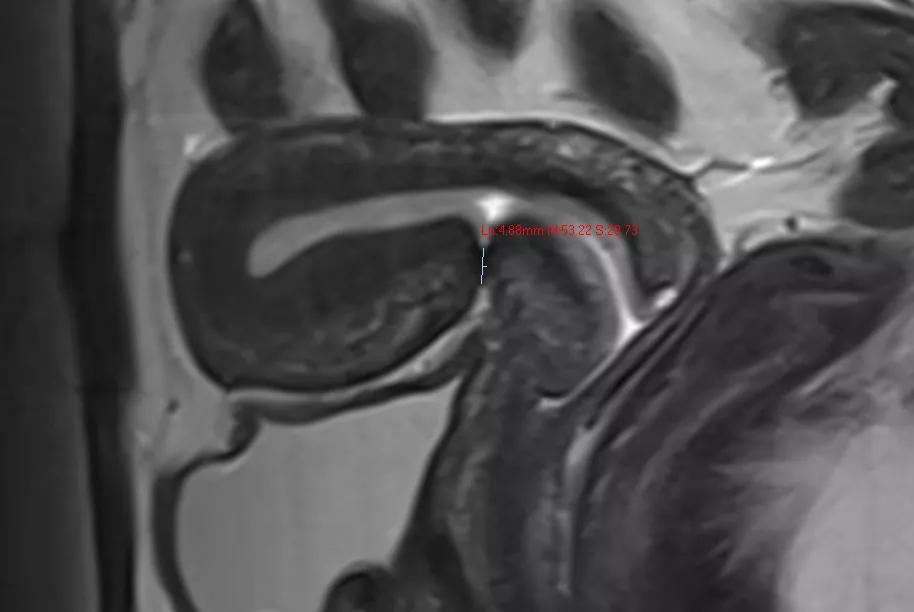

图2 CSD主要表现为子宫瘢痕处存在子宫肌层不连续,出现三角形、楔形、半圆形或不规则形的缺损,并与宫腔相通。

关于CSD的分类与分级方法众多且缺乏统一标准,主要通过测量CSD的深度、宽度、长度、残余肌层厚度(residual myometrial thickness,RMT)、毗邻肌层厚度(ajacent myometrial thickness,AMT)及距离宫颈内口的距离等指标综合评估。文献报道最多的是按照肌层缺损范围分为大CSD和小CSD, 常用的诊断阈值包括:深度与子宫壁厚度(RMT+深度)的比值≥50%(或80%),或TVUS-RMT<2.2mm或SHG-RMT<2.5mm;当憩室顶端仅覆盖浆膜层时,可诊断为完全性CSD。

图3 MRI检查T2WI矢状位可清晰显示并测量子宫瘢痕处缺损的深度,残余肌层厚度等参数,为CSD的分级及再次妊娠的评估、随访提供高价值医学影像支持。